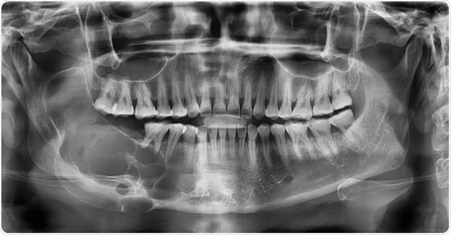

(우리 데스크 선생님 파노라마 사진입니다 ㅎㅎ)

아래는 환자분의 파노라마 X-ray입니다.

생각하지 못한 문제가 발견되었습니다. 무엇일까요?

표시한 부위에 검은 음영이 관찰됩니다.

보통 건강한 치조골(잇몸뼈)은 X-ray 상에서 하얗고 회색빛의 결 구조가 나타나는데,

이처럼 어둡고 비어 보이는 음영은

염증 등으로 인해 뼈 조직이 약해졌거나 흡수되었을 가능성을 의미합니다.

해당 부위는 크기도 꽤 큰 편이어서,

더 정밀한 진단을 위해 CT 촬영을 진행하기로 했습니다.